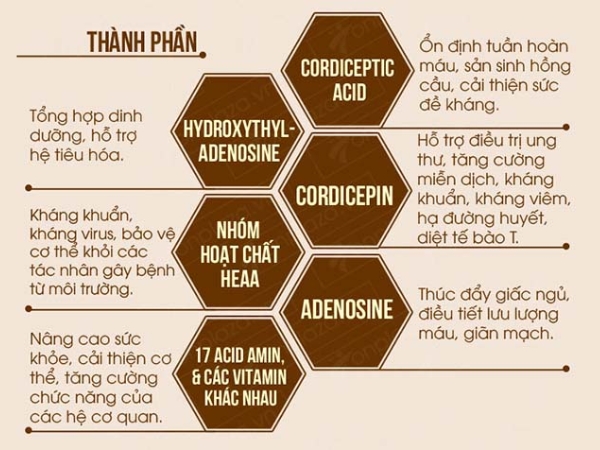

Cordyceps Sinensis, còn gọi là đông trùng hạ thảo, từ lâu đã được xem như một dược liệu quý trong y học cổ truyền nhờ vào khả năng tăng cường sức khỏe toàn diện. Loại thảo dược này chứa nhiều thành phần quý giá, bao gồm các axit amin, vitamin và khoáng chất, giúp cải thiện hệ miễn dịch, hỗ trợ chức năng gan, phổi, và tăng cường sinh lý. Dưới đây là những tác dụng nổi bật của Cordyceps Sinensis đối với sức khỏe con người.

Cordyceps Sinensis có khả năng hỗ trợ hệ miễn dịch, giúp cơ thể chống lại các vi khuẩn và virus gây bệnh. Loại thảo dược này kích thích sự sản xuất và hoạt động của các tế bào miễn dịch, giúp bảo vệ cơ thể trước các tác nhân gây hại từ môi trường.

- Công dụng của Cordyceps Sinensis với hệ miễn dịch: Các nghiên cứu cho thấy Cordyceps Sinensis giúp tăng cường miễn dịch tự nhiên, hỗ trợ cơ thể chống lại các bệnh nhiễm trùng, cảm cúm và các bệnh thường gặp khác.

- Tăng cường sức đề kháng: Loại thảo dược này đặc biệt có lợi cho những người có hệ miễn dịch suy giảm, bao gồm người già và những người bị căng thẳng kéo dài.